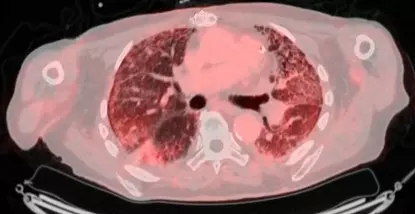

Pour aller plus loin dans la lutte contre cette maladie, le service de Pneumologie de l'Hôpital Erasme a initié une collaboration étroite avec le service de médecine nucléaire (Professeur P. Flamen et le Dr A. Deleu) pour développer un projet novateur d'imagerie moléculaire par PET/CT dans le but de visualiser l'activité de la maladie : le projet FAPI-PET.

​Le principe est d'utiliser un traceur radioactif qui va se lier aux cellules qui fabriquent la fibrose, les fibroblastes. Cette technologie révolutionnaire a déjà fait l'objet d'une première étude prometteuse sur 50 patients, financée grâce aux donateurs du Fonds Erasme. Les résultats, d'ores et déjà présentés lors d'un grand congrès européen de pneumologie et prévus pour une présentation actualisée à Barcelone, sont particulièrement excitants. L'équipe médicale a identifié un seuil (cut-off) du SUVmean : si l'activité mesurée au PET scan dépasse ce seuil, il est possible de prédire avec une sensibilité et une spécificité supérieures à 90 % que la maladie va progresser dans l'année avec un risque significativement plus élevé de décès.